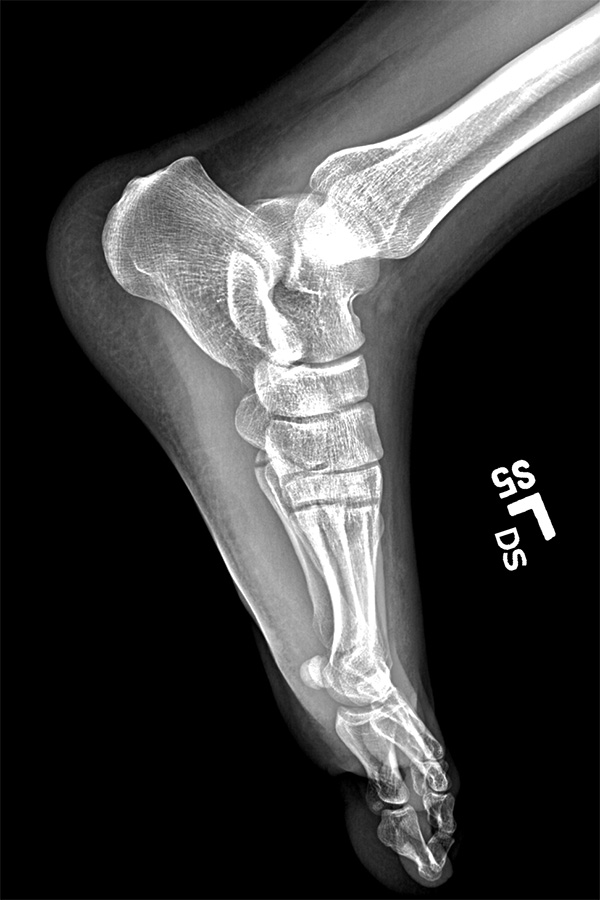

i had nothing to lose and was curious to get my hands on my broken foot x-rays from last year 2 years ago, so i went to the sub-basement of the bigelow building. i wasn't sure if i could get it today, and i wasn't sure if i had to pay. the man who helped me said he'd put everything onto a disc, and that he could do it while i waited. what i thought would be a quick wait ended up being almost 45 minutes. the big hold up were the MRI scans, which i already had a copy. was he downloading the images via 1990's modem technology? i also learned that if you request the images for personal use then you'd have to pay, but it's not seriously enforced, and if you just make up a doctor, you can get everything for free (they give you the disc anyway, they don't mail it out).